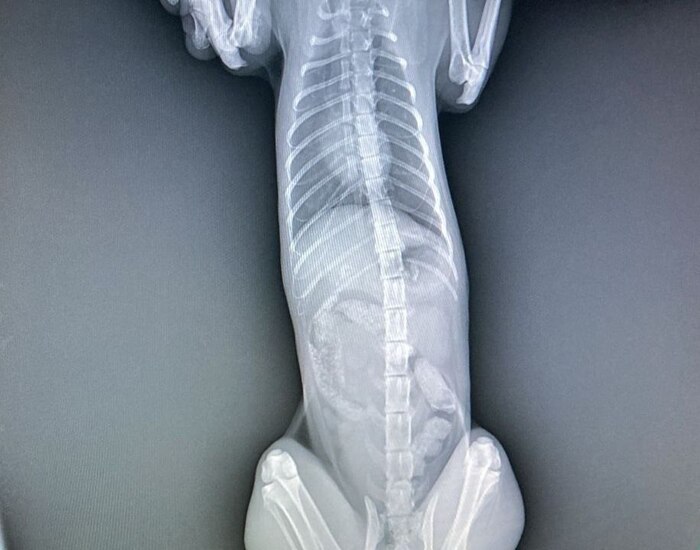

Всем привет! У меня есть кот, подобрал пару лет назад, сбитого, на обочине, без сознания. Сначала он был совсем не очень живым, но после двух недель в стационаре вроде поправился(немного шокирован был от того сколько стоит лечение). После того, как забрал домой, кот понятное дело долго приходил в себя, ходил не очень уверенно, не очень понимал что происходит. Периодически были видны последствия черепно-мозговой травмы(невозможность сконцентрироваться на одном объекте, я так понял, т.к он постоянно провожал взглядом непонятно что с одной стороны в другую и так по кругу(хз как по другому объяснить). Потом окреп и стал более уверенным, есть еще кошка и кот, с котом подружился, с кошкой до сих пор нет. Так вот проблема в том, что после того как он более менее пришел в себя - начал ходить по квартире и просто кричать, сначала было терпимо, потом невыносимо. Купил успокоительные в вет. аптеке - вроде сначала успокаивали, потом какие то нервные срывы бесконтрольные начались, перестали давать таблетки. Прошло какое то время и он стал обычным ленивым котом. Но пару месяцев назад он опять начал ходить из угла в угол и орать, мы уже привыкли, но хочется это изменить, он может несколько часов подряд ходить и кричать, потом дышит как пес, отдохнет 10-20 мин и опять ходит. Если знаете, что делать или к какому конкретно врачу обратиться - подскажите пожалуйста. Учитывая невозможность проверить чисты ли на руку вет. клиники, хотелось бы сразу попасть к нужному специалисту, а не выкинуть много денег на обычные - «У вас отличный кот, спасибо, что показали». Спасибо. Плюсаните пожалуйста, хочется, чтобы Олег перестал переживать)